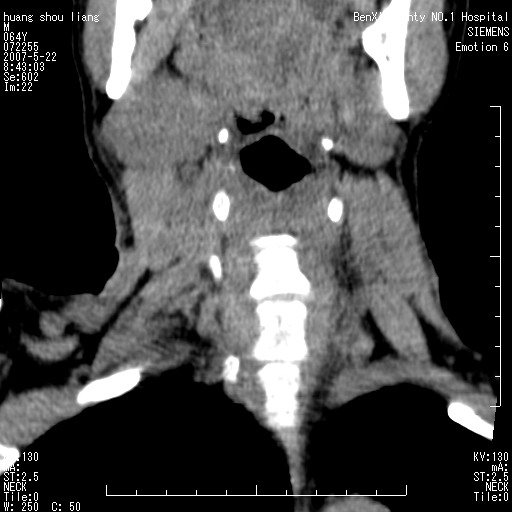

男性,64岁。颈部包块8年。最近增大。

对不起大家,可能是片子发太多有点乱,正常腮腺在下颌角的外侧,颌下腺在下颌体的中部内侧,本例在下颌角内侧偏下,和腺体一点关系都没有,从vrt和mpr上可以很明显看出来,再者肿块是好多粘连在一块的,大家在仔细看看,左侧可能也是吧,我还是考虑为肿大的淋巴结融合在一块,但性质??????

右侧腮腺下部均匀软组织密度肿块,外形不规则,与周围组织分界清晰,考虑右侧腮腺混合瘤或多形性腺瘤。

大家好,病理结果出来了,如大家所说,颌下腺混合瘤。

唉,解剖没学好吧,我诊断错了,不过还是有些不理解回去我在多看看书,谢谢大家的参与,以后我还会奉献好的病例。